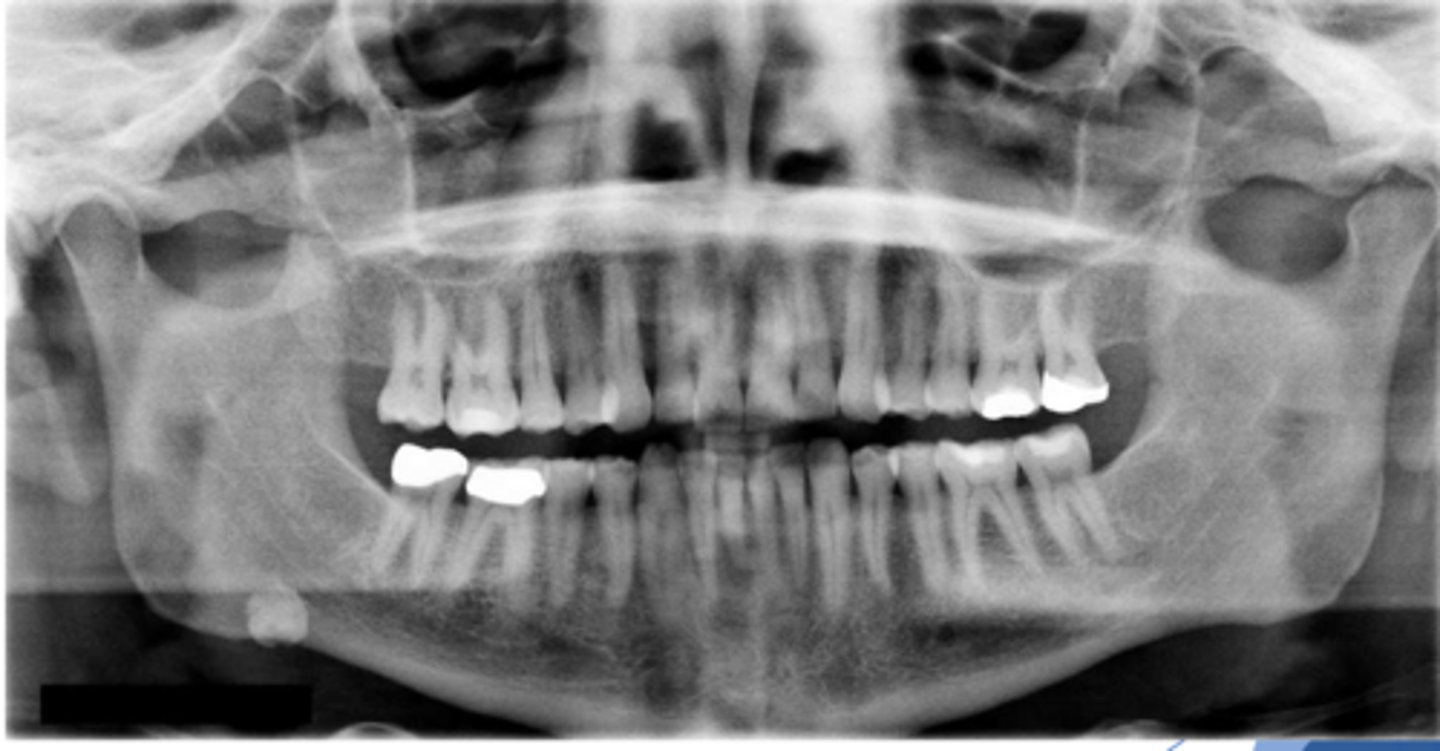

Patient present to your office complaining of pain upon salivation. A small firm, non-fluctuant mass is visible on the floor of the mouth lateral to the midline. Radiograph shows a radiopaque mass in the location of interest. What is the diagnosis?

Sialolithiasis

ID the pathology:

Swelling in wharton's duct

ID the pathology during surgery:

Associated with pain upon salivation

What pathology is associated with pain upon salivation?

submandibular gland

80% of Sialolithiasis are associated with what gland?

Radiopaque mass

What is the radiographic features of a

Sialolithiasis?

ID the pathology based on the histology findings:

- Laminated calcified structure with central nidus

- Milking stone toward duct orifice

- Sialologues

- Surgical removal

- Lithotripsy

What is the treatment for Sialolithiasis (4)?